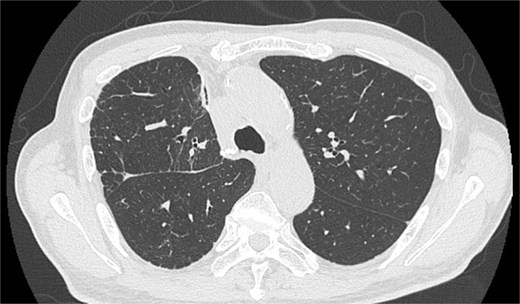

After the reoperation, AL was not observed, and SE regressed. The chest tube was removed on POD 5 after the reoperation (POD 16 after initial surgery). The patient was discharged on POD 18 after initial surgery. CT performed after 1 year revealed no emphysema or cancer recurrence (Fig. 3). The patient was informed of the complications and accepted the treatment outcomes.